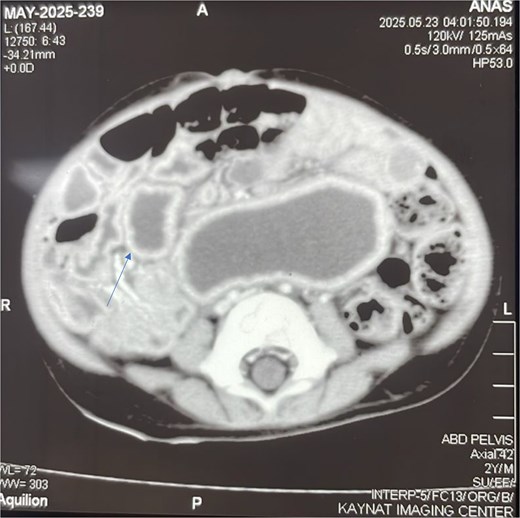

To better characterize this lesion, a contrast-enhanced computed tomography (CT) scan of the abdomen and pelvis was performed. The scan (Fig. 2) revealed a well-defined, thick-walled cystic lesion in the midgut region that demonstrated peripheral post-contrast enhancement without internal septations or solid enhancing components. Its intimate location along the mesenteric border of the small bowel was highly suggestive of an enteric duplication cyst.

Contrast-enhanced axial CT scan of the abdomen. The image reveals a well-defined, thick-walled cystic lesion (arrow) located along the mesenteric border of the midgut. The lesion demonstrates peripheral post-contrast enhancement without internal septations or solid components, findings highly suggestive of a jejunal duplication cyst.